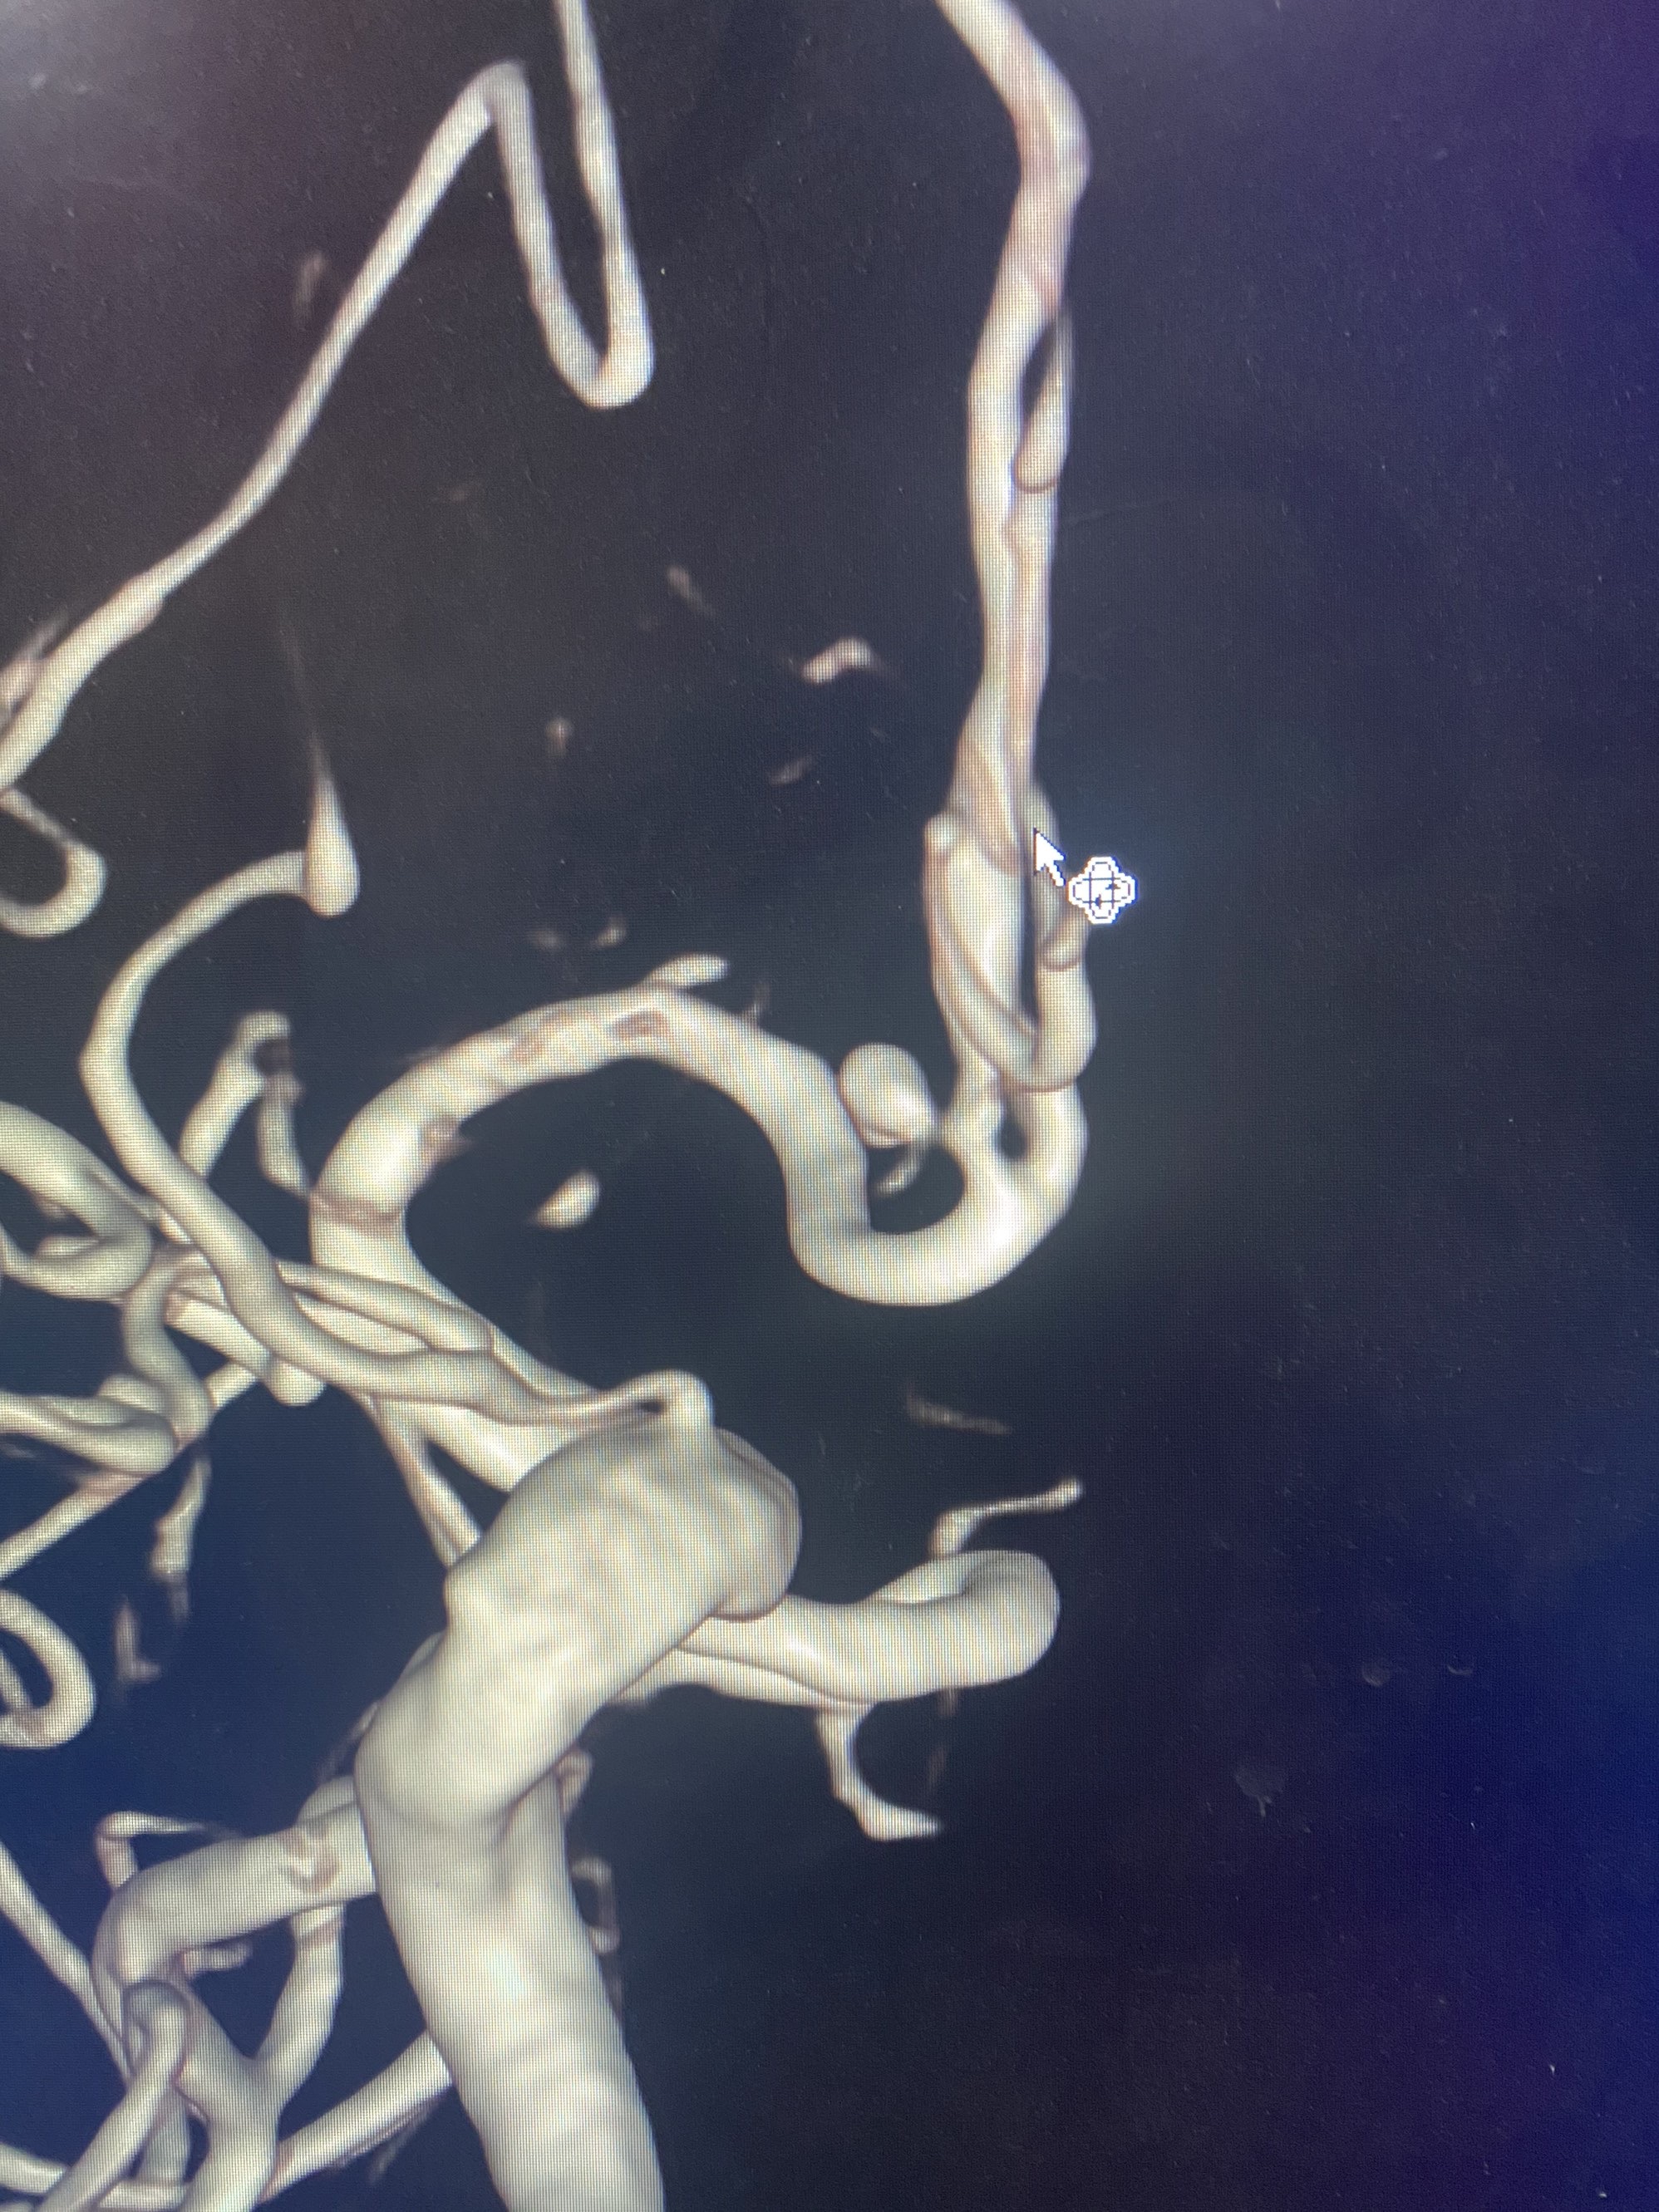

MLS,M79Y,sah,双侧MCA烟雾病,Heubner返动脉瘤,前交通段开窗,细支发出Heubner返动脉,瘤颈细长,瘤颈口比微导管细,弹簧圈2mmx3cm“隔山打牛”填塞治愈,Heubner返动脉保留。

该患者术后2天观察神志清楚,四肢活动正常。

Heubner返动脉是由大脑前动脉A1末端发出的豆纹动脉,由于走形和A1段相反,故称Heubner返动脉,该动脉梗塞可能引起尾状核头梗塞,引起偏瘫和面瘫,便身震颤等症状。